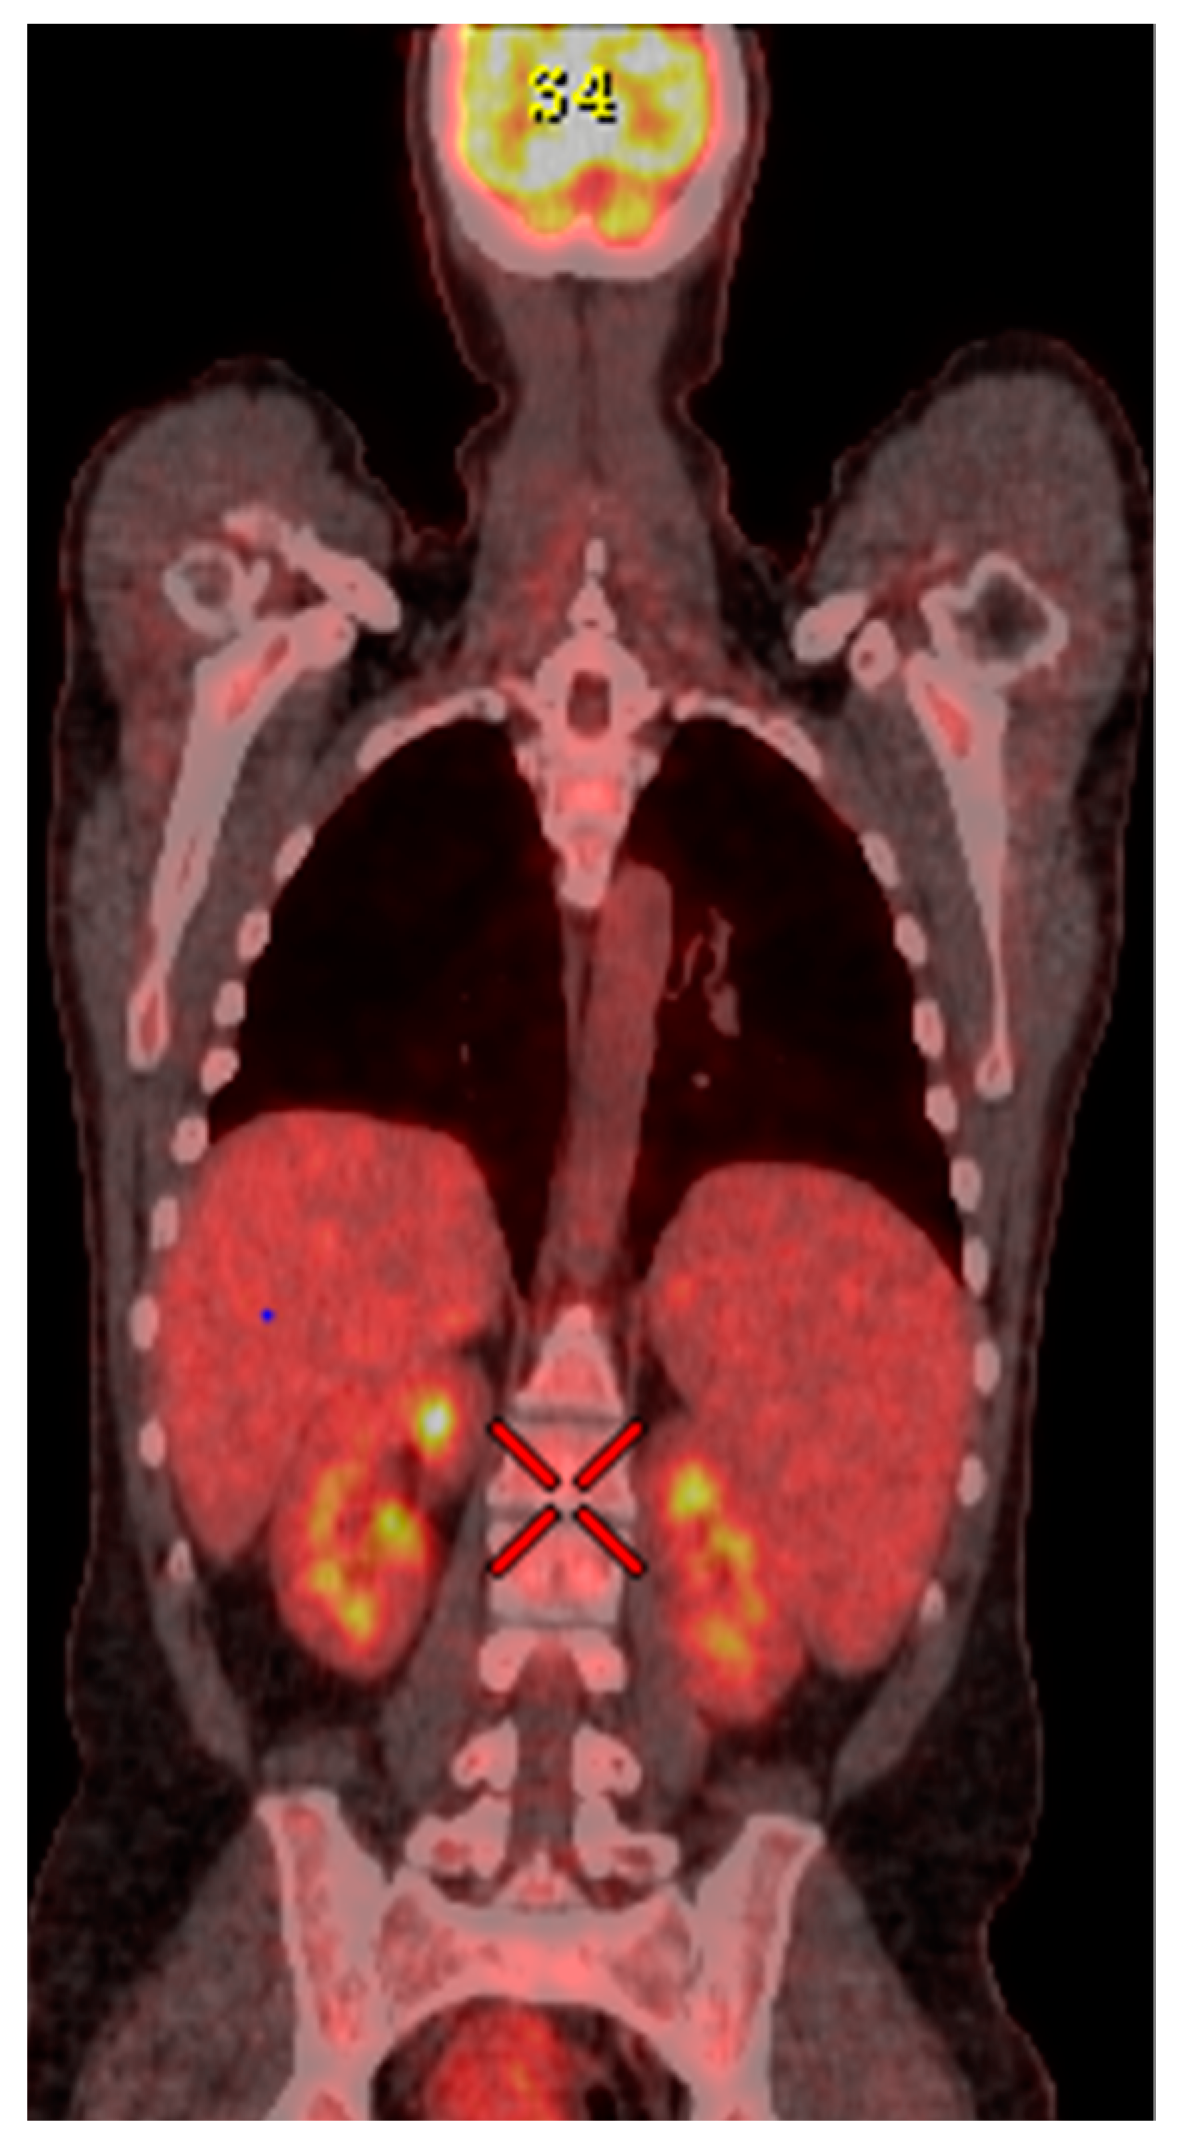

2. Case Presentation